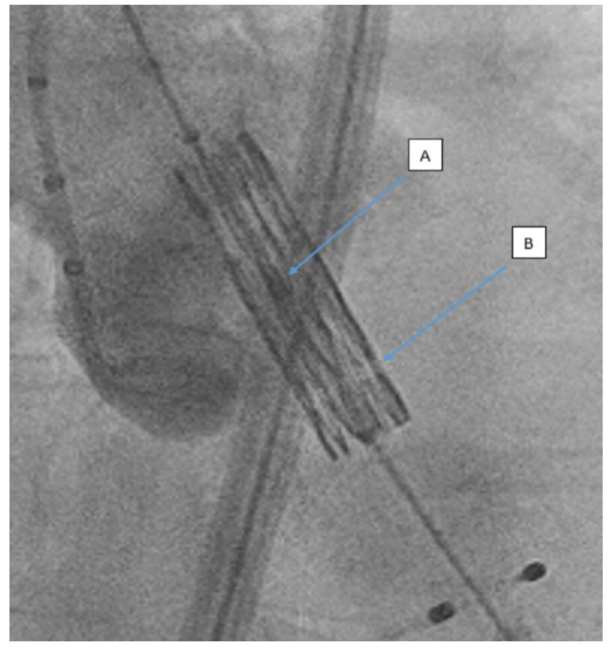

Evaluating THV deployment depth. All fluoroscopic imaging was reviewed by an operator independent of the index procedure (JM) and blinded to clinical outcomes. Images were calibrated with the graduated pigtail catheter used for aortography. The distance from the bottom of the THV balloon marker to the top of the line of lucency on the stent frame was measured. The annular plane was then annotated immediately prior to THV deployment. Figure 2 and Figure 3 demonstrate the relevant landmarks used to evaluate THV predeployment depth relative to the annular plane in a 3-sinus fluoroscopic view.

Implantation depth was defined as low if the balloon marker to annular distance was less than 25% of the total distance from balloon marker to the line of lucency, intermediate if this measurement was between 25% and 50%, and high if it was greater than 50%. There were no implants that positioned the line of lucency superior to the annular plane at the point of THV deployment.

A high implant therefore positioned the line of lucency closer to the annular plane at the point of deployment and a low-intermediate implant positioned the balloon marker closer to the annular plane. Figure 4 depicts the classification of predeployment depth in relation to both balloon marker and the line of lucency. Following deployment, the final implantation depth was measured. This was then expressed as the percentage of the implanted THV stent frame that lay on the aortic aspect of the annular plane.